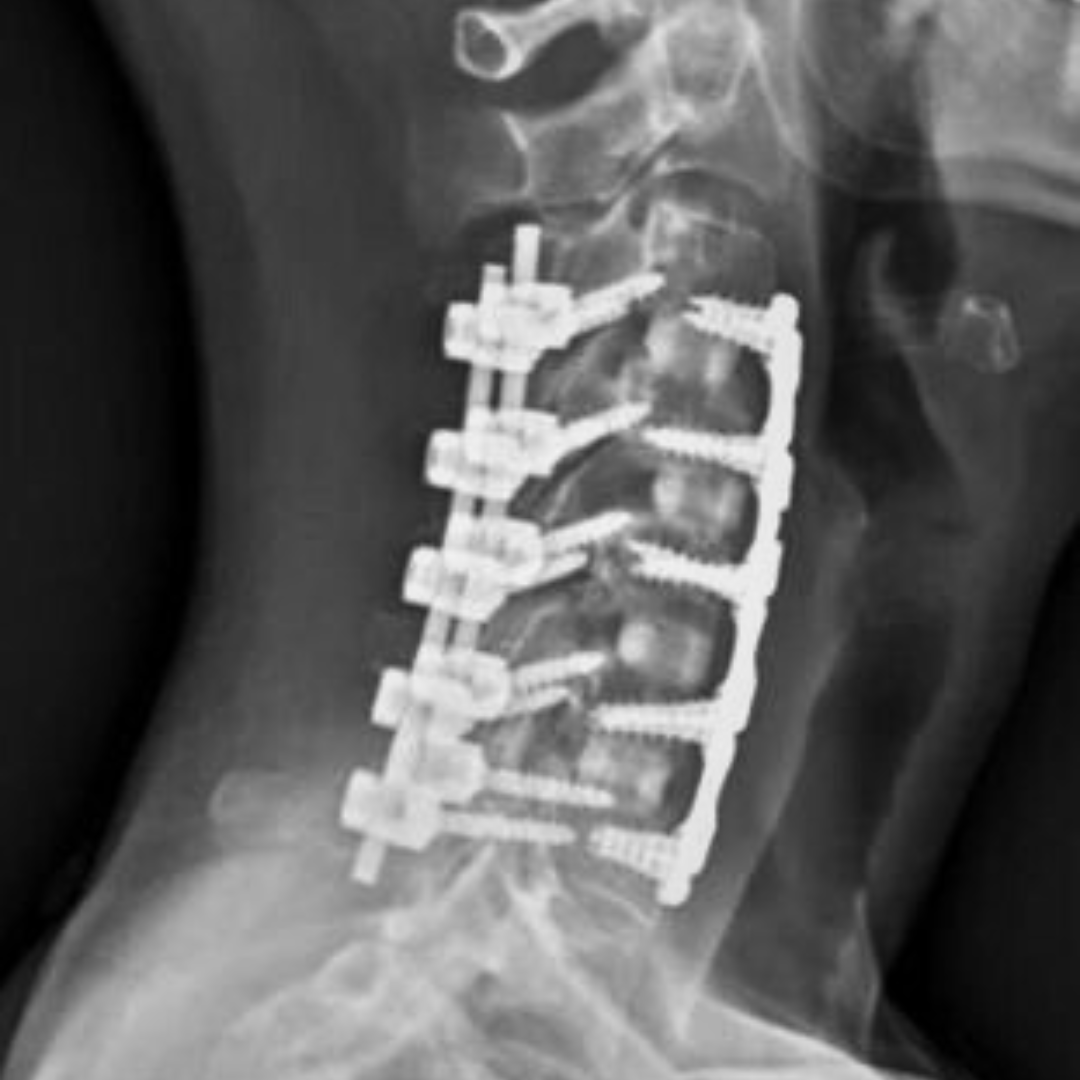

After being transported to the hospital, the early prognosis was not good. X-rays showed he had suffered a complete break in his vertebrae. He was paralysed from the neck down and doctors believed the damage to his spinal cord was likely permanent.